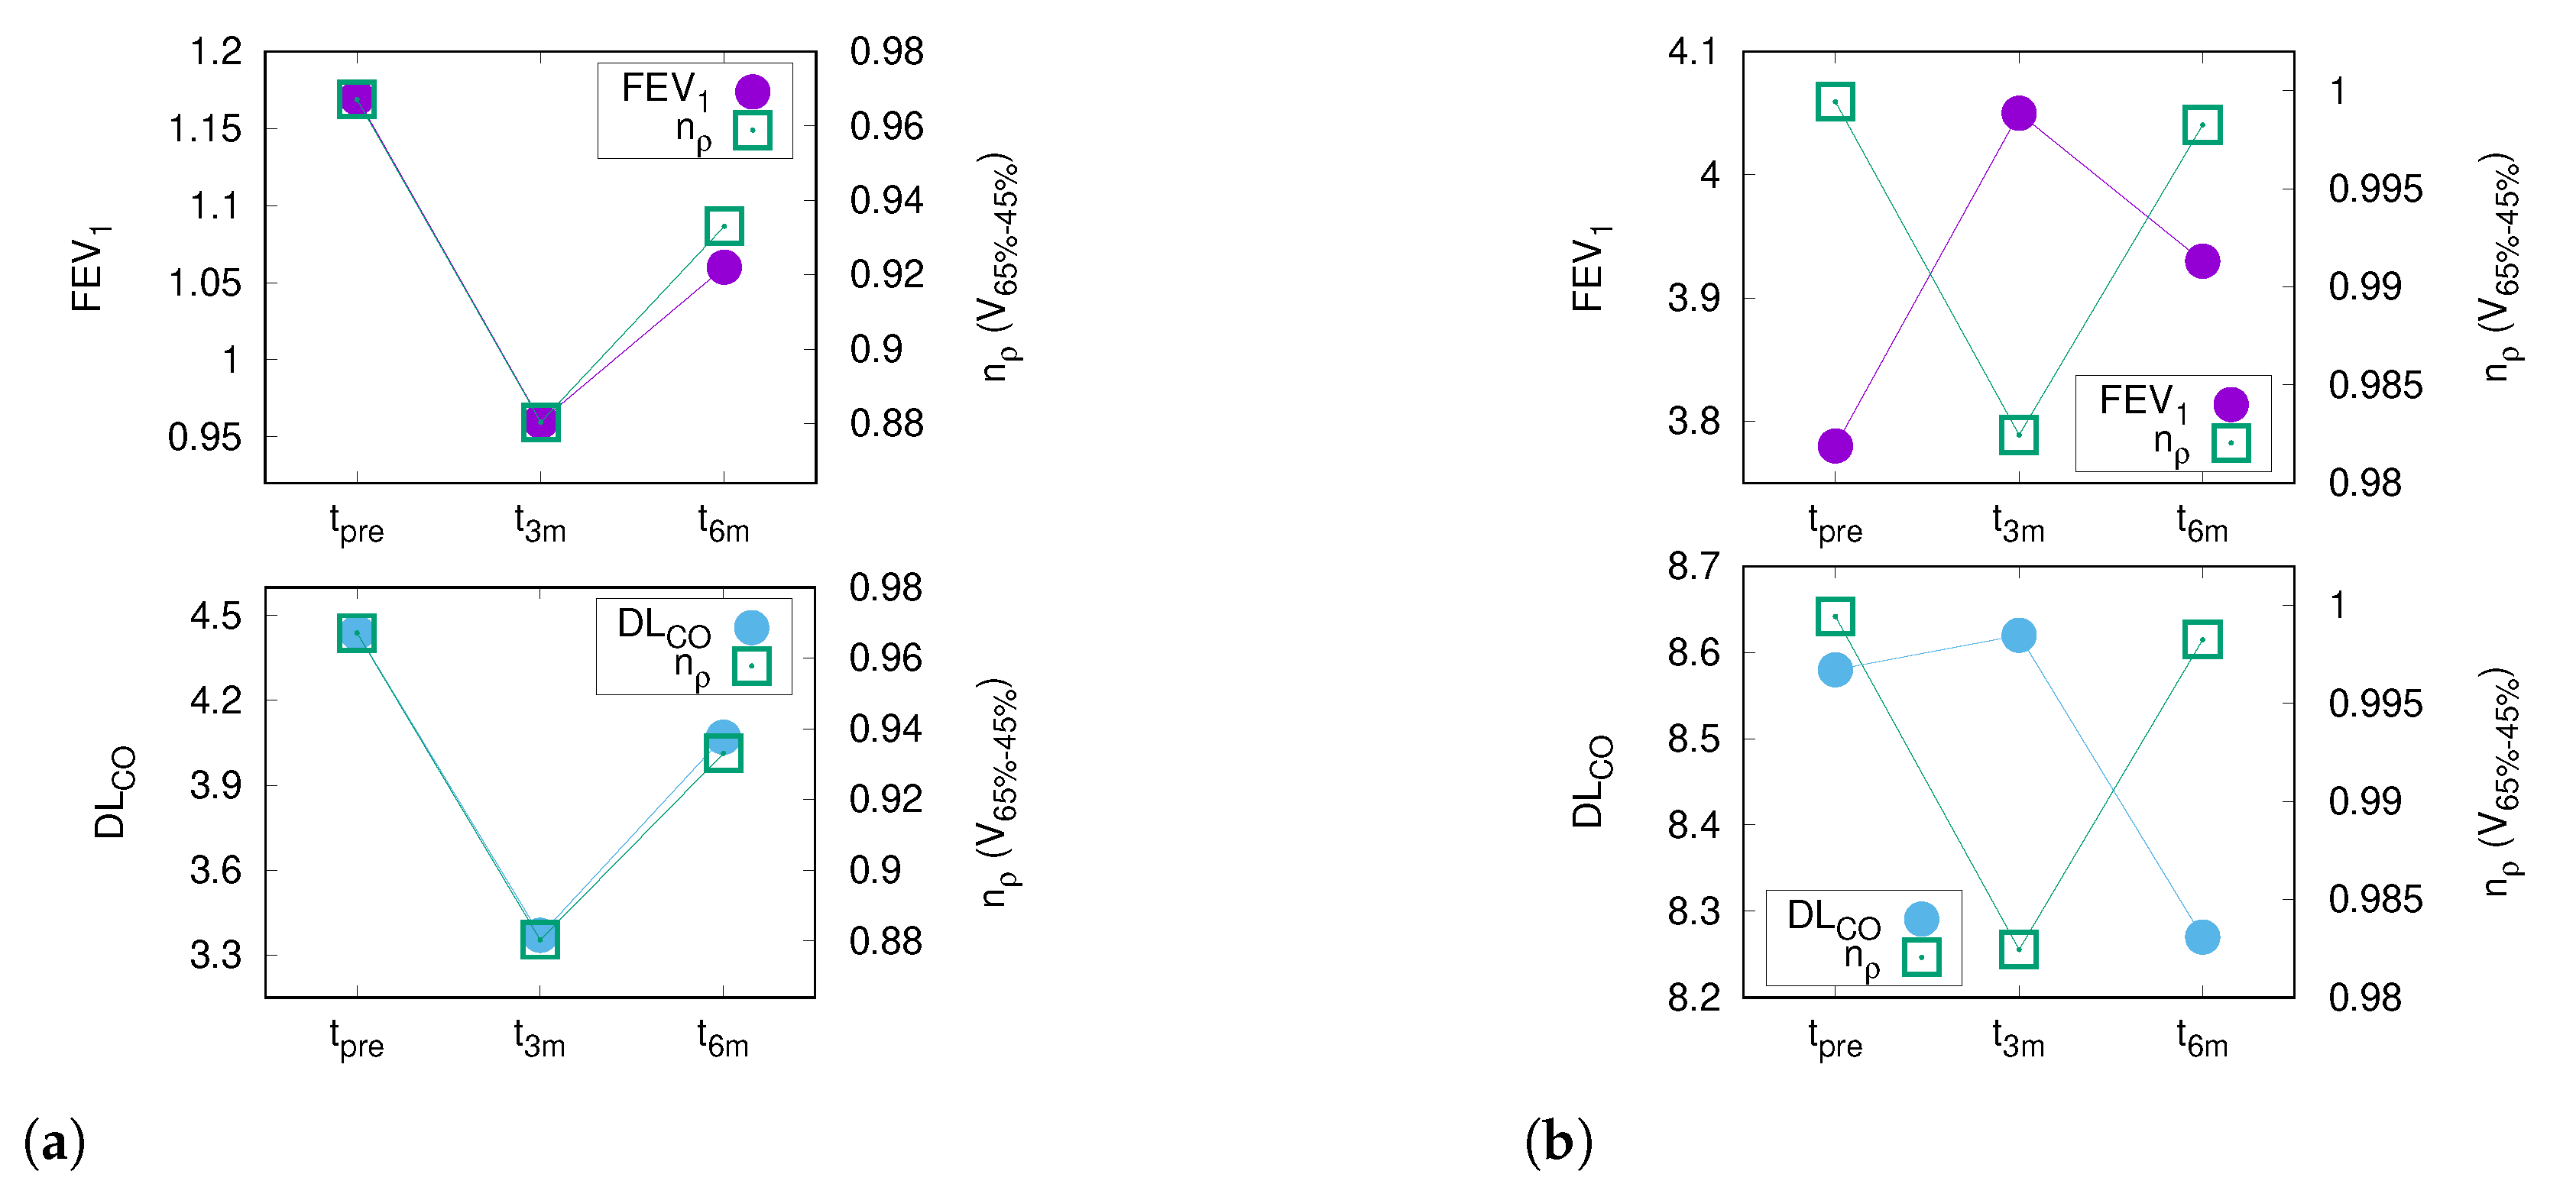

3.5. DL Correlates with V

3.6. PFT and CT Density Changes after RT

3.7. DL after RT Is Predicted by V